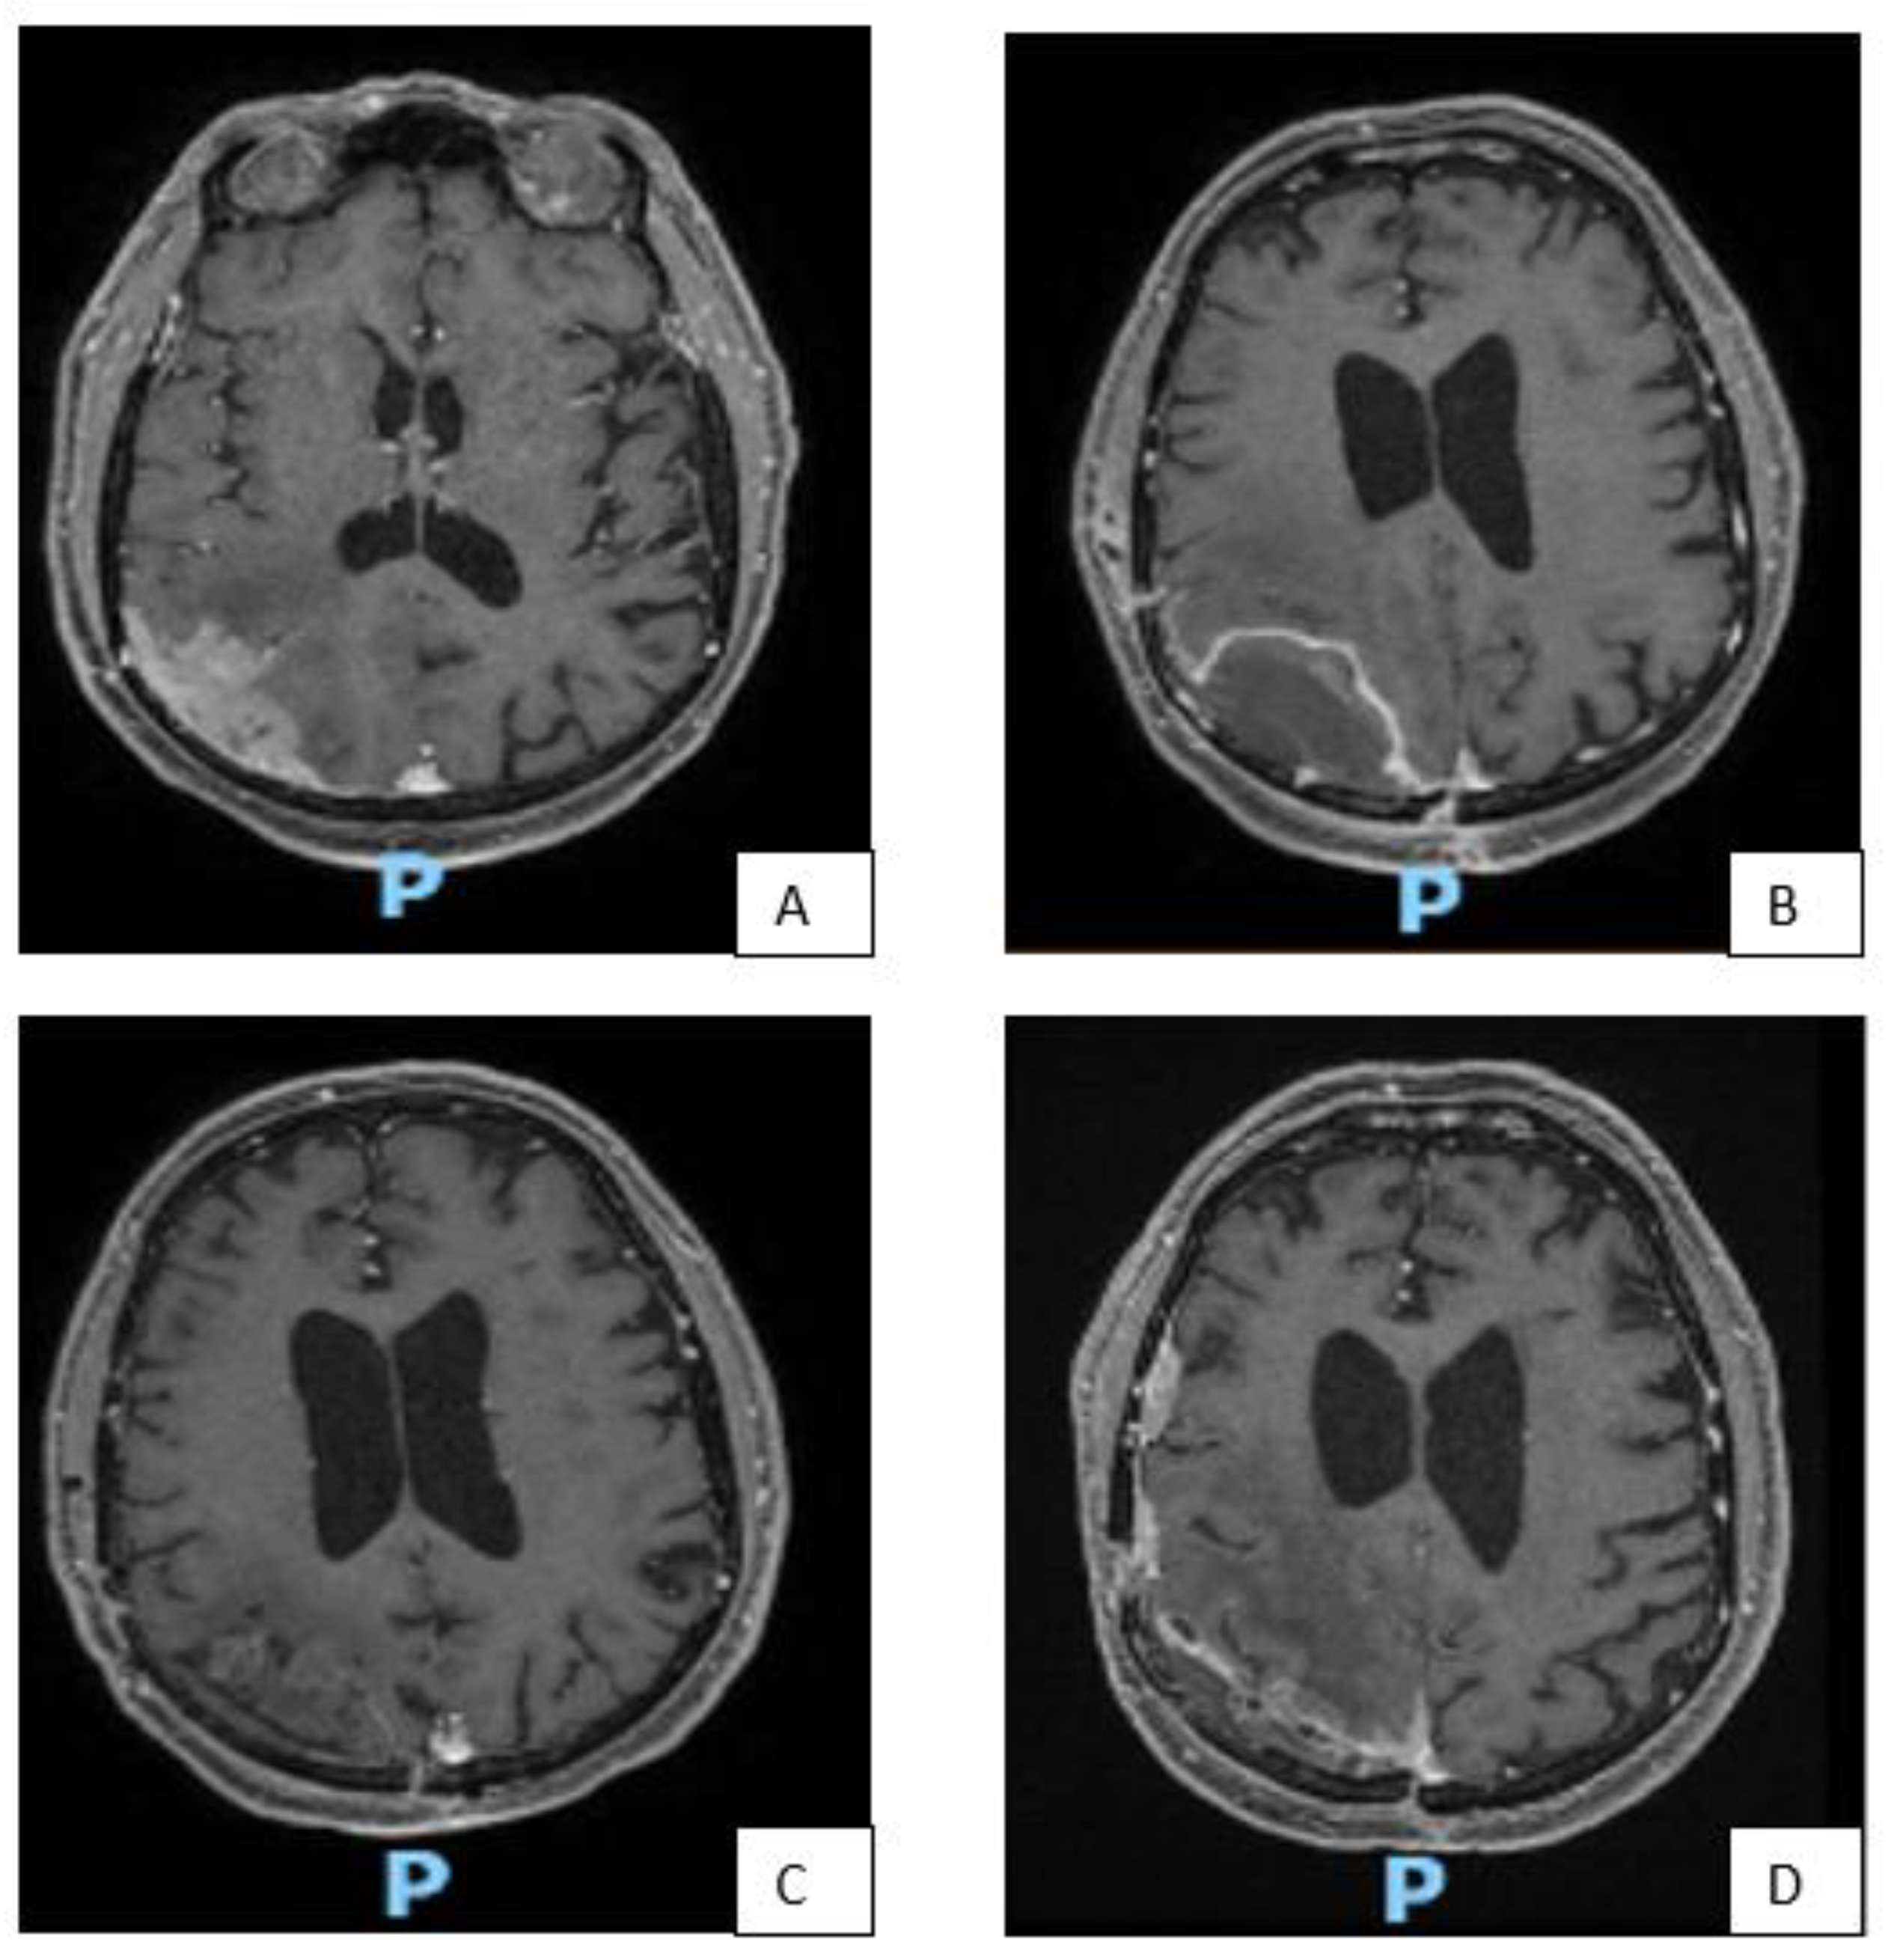

In Figure 3 some illustrative cases are reported.

Figure 3.

MRI images of some representative cases. Patient with right fronto-parietal convexity meningioma (A), subjected to GTR (Simpson I), as can be seen from the post-operative brain MRI (B). Due to the pathological features (high number of mitoses and cerebral invasion) the patient underwent adjuvant RT treatment despite surgical removal Simpson I. Good local control after two years from adjuvant RT (C). After 36 months, appearance of distal recurrence (D). MRI of a patient with multiple meningiomas (E). Patient with large left frontal meningioma, subjected to surgical removal (F), associated with two other nodules at the left sphenoidal wing, subjected to GKRS (G). Picture (H) shows good disease control 4 years after GKRS treatment. GKRS for a small recurrence of left frontal convexity meningioma (I) and relative MRI control 18 months after (J). GKRS for two nodules of right fronto-temporal meningioma (K). 15 months after radiosurgery, a new GKRS was performed on a further nodule of recurrence at the sphenoidal wing (L).

In our series, the only patient in whom the adjuvant RT treatment was performed in a Simpson I, presented angiomatous aspects on histological examination with some microfocal areas of anaplastic change. This patient had local recurrence 36 months after surgery, despite RT of the surgical cavity, with important radionecrosis causing hemiparesis and medically poorly controlled epilepsy (Figure 3A–D). As shown in Figure 1 60% of patients with Simpson I surgical removal and observation, remained stable, while the percentage of stable in the Simpson II/III category fell to 25% (5 out of 20 patients). The only 2 patients with Simpson II/III treated with adjuvant GKRS, had stable follow up at 2 years.